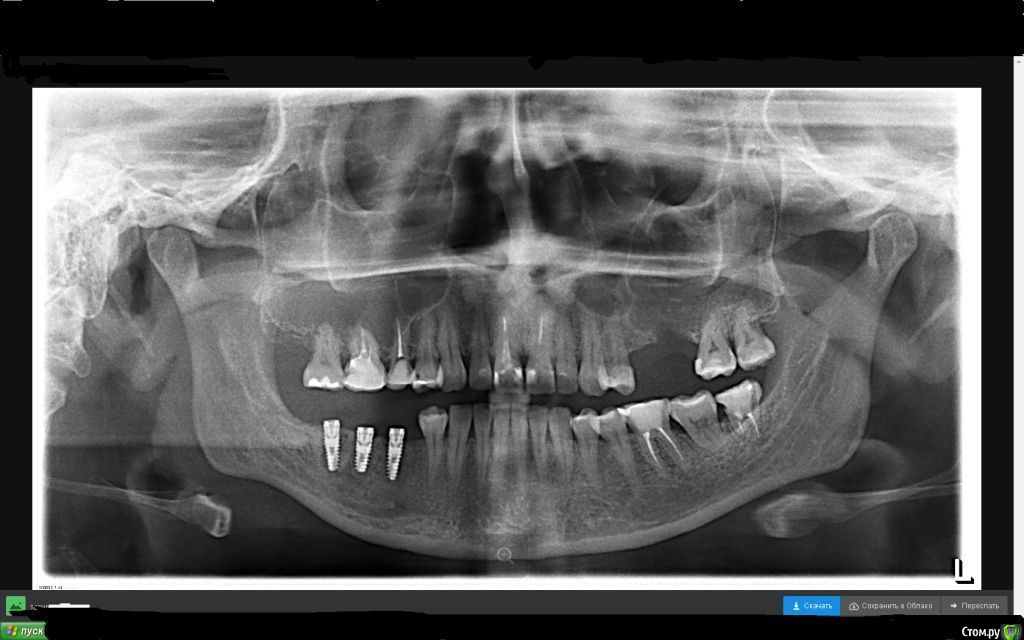

kobra141480 Опубликовано 31 января, 2017 Автор Поделиться Опубликовано 31 января, 2017 доктору за семьдесят? Фото во рту покажите. Сколько прошло времени после имплантации?Да, лечащему доктору около 70 и я боюсь, что он на эстетику не обращает внимания. С момента имплантации прошло ровно 7 месяцев, имплантат на месте 5-ки долго приживался.http://s018.radikal.ru/i528/1701/00/7e1d2cba90a0.jpgснимок.bmp Ссылка на комментарий

red_butler Опубликовано 31 января, 2017 Поделиться Опубликовано 31 января, 2017 первый имплант я бы переставил, и отработать мягкие ткани Ссылка на комментарий

red_butler Опубликовано 31 января, 2017 Поделиться Опубликовано 31 января, 2017 даже не смотря на то, что он хорошо прижилсяхорошо прижился понятие относительное, у Вас не просто прорезалась заглушка, это более 1 мм импланта выступают в полость рта и по Rg потеряно кости до 1/3 длины винта. Если Бы эти импланты были установлены мною, то первый я бы переставил.А так побороться конечно можно. Да, и еще. А ортопед Вас давно смотрел? Ссылка на комментарий